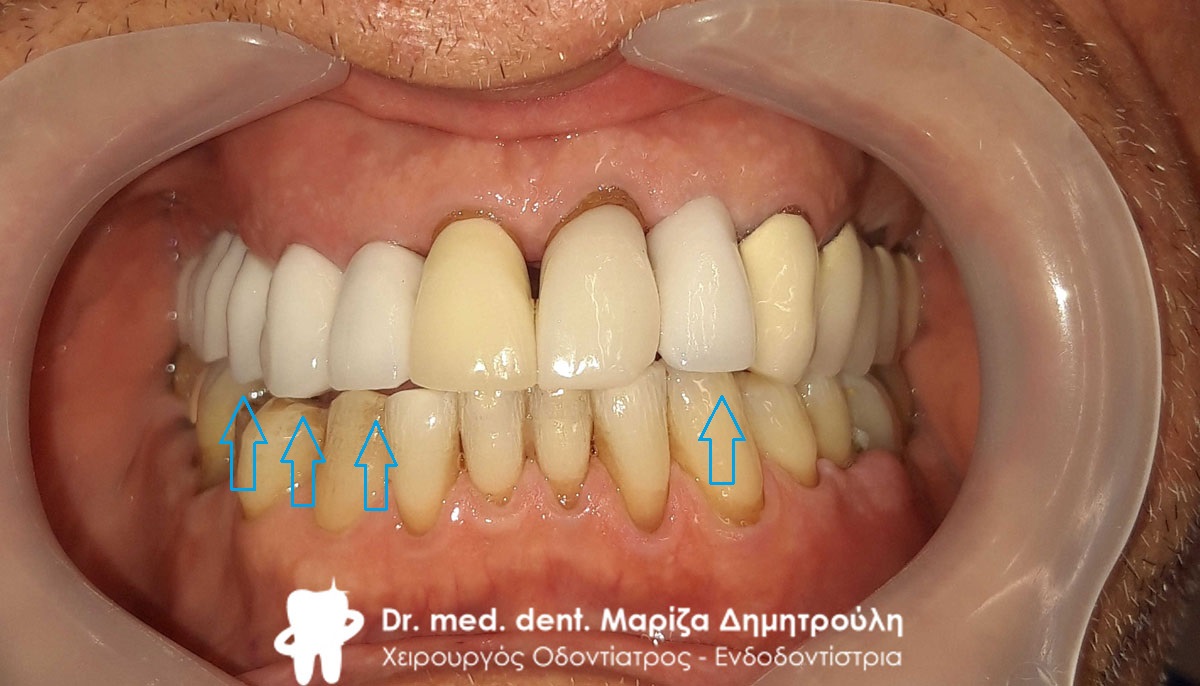

Ο ασθενής επισκέφτηκε το ιατρείο με σκοπό την αποκατάσταση του μεγάλου ελλείμματος στη δεξιά πλευρά της άνω γνάθου όπως επίσης και την αντικατάσταση μιας παλιάς θήκης στη δεξιά πλευρά της άνω γνάθου. Όπως δείχνουν και οι φωτογραφίες πραγματοποιήθηκε και αντικατάσταση παλιών λευκών σφραγισμάτων στη δεξιά πλευρά της κάτω γνάθου.

Αρχική εικόνα